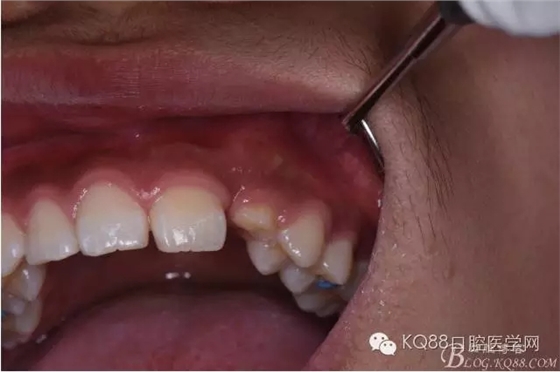

图6.口内观:63滞留、23未见萌出。

图7. 腭侧夜未见明显的隆起